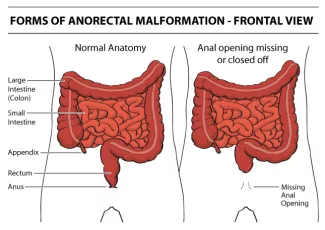

Anorectal Malformation, aka Imperforate Anus, is a spectrum of abnormalities of the rectum and anus. There are many possible abnormalities as follows:

- The absence of an anal opening.

- The anal opening in the wrong place.

Since each child’s specific anatomic abnormality will vary, it is important for you to understand your child's particular anatomy.

The diagnosis is made by physical examination. If the anal opening is absent or in the wrong spot, it can be seen on examination. If there is stool coming out of the urethra, or vagina, instead of the anus, it will be visible. In females with anorectal malformation, careful examination of the vestibule (area between the labia) must be made to ensure separate openings of the urethra and vagina. In the males with imperforate anus, careful examination of the perineum is necessary to identify any abnormal passage of stool.